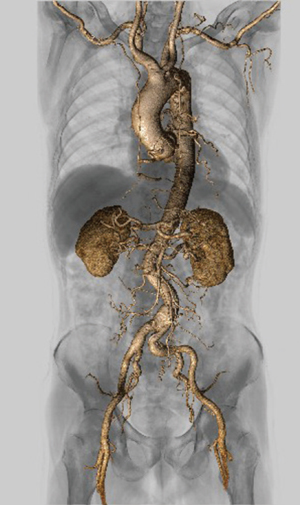

高い認識精度で3D画像作成を支援するAbierto Vision(図3)

今回、Aquilion ONE / INSIGHT Editionの導入に合わせてAbierto Visionが稼働した。Abierto Visionは、AI技術によるさまざまな部位のセグメンテーションで高度な画像解析を可能にした医用画像解析WSとして、2024年11月に発売された。Abierto Visionでは、「Auto Extract」によってワンクリックで、頭頸部、体幹部、下肢の骨の分離抽出、脳動静脈の分離抽出を可能にするほか、冠動脈芯線をトラッキングする「Coronary Tracking」など、3D解析のワークフローを簡略化する技術を搭載している。そのほか、同社のWS「Vitrea」に搭載されていたベイズ推定法を用いた「CTボリュームパフュージョン解析(CTP解析)」などのソフトウエアも利用できる。

3D画像作成は、Abierto Visionのほか他社製WSも使用して、CTAや整形外科領域などを中心に1日約30件を作成している。3D画像の作成は技師全員が行えるようにしているが、稲垣係長は、「日替わりで担当は決まっていますが、撮影補助なども兼務しながらなので、3D画像作成に専念することができません。それだけに、Abierto Visionで自動抽出の精度が向上し、件数の多い大動脈や下肢、頭部のCTAで血管が精度良く短時間で処理されれば、3D画像処理の時間短縮にもつながるのではと期待しています」と述べる。田中部長はAbierto Visionの導入効果について、「自動化によって3D画像作成の時間が短縮して、働き方改革につながるといいですね」と言う。

図3 大動脈解離

高速ヘリカルスキャンとAbierto Visionで

全身血管を描出